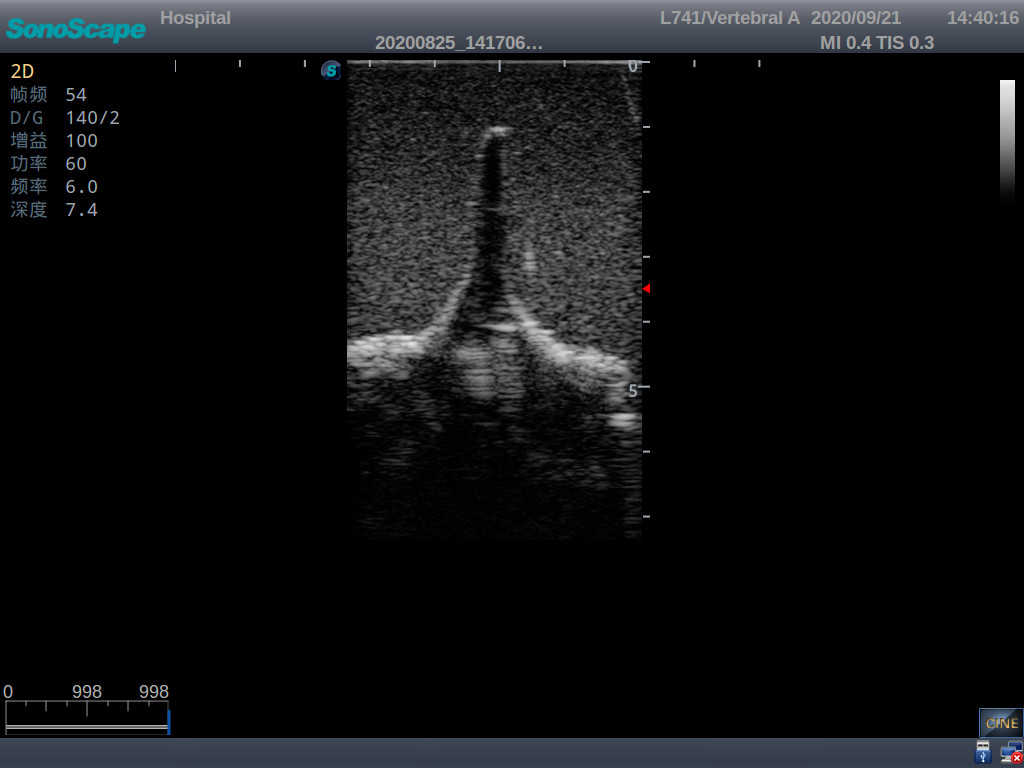

This model is an ideal choice for ultrasound-guided adult lumbar puncture training with true-to-life skin feel and touch, accurate anatomical structures as well as real clinical ultrasound images. Realistic resistance to needle tips and correct landmarks provide excellent hands-on experience.

2)  Real clinical ultrasound images

1)   Ultrasound-guided lumbar puncture practice